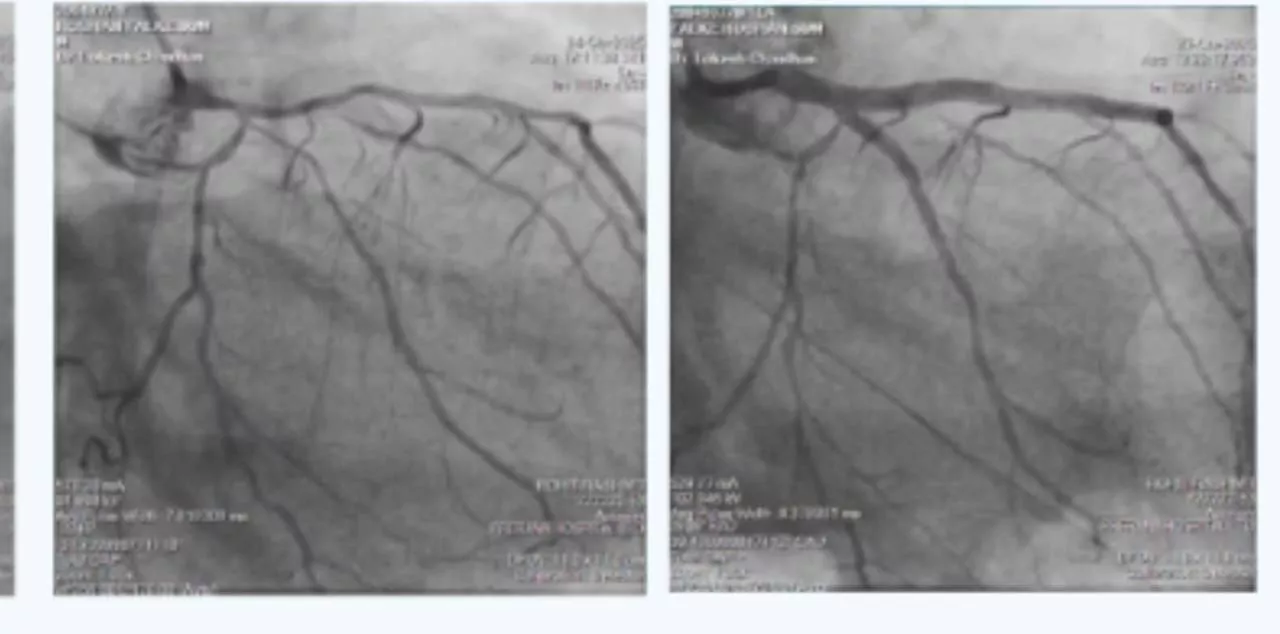

On arrival had mild dyspnea, no chest discomfort but had severe right lower limb pain since 6 hours, hence was started on heparin infusion and bilateral lower limb CT peripheral angiography was done which revealed Bilateral lower limb severe peripheral vascular disease with occlusion in bilateral femoral arteries and distal reformation through collaterals. Gradually patient was stabilized with heparin infusion alone. After 5 days, creatinine came to baseline of 1.5 and angiography wad done which showed Critical Left main with Triple vessel disease as shown in angiogram pictures. Patient had Right coronary artery in-stent-chronic total occlusion with filling of distal RCA from collaterals from LCA; Distal Left main had 80% narrowing with proximal LAD 70% and proximal LCX 80% stenosis.

In view of multiple comorbidities and patients preference, high risk complex multi-vessel PCI (Including RCA-ISR-CTO & LM-LAD-LCX bifurcation) was planned and done as per plan under local anesthesia from right radial artery access as CT aerogram showed diffuse peripheral vascular disease starting from abdominal aorta extending into bilateral femoral arteries.